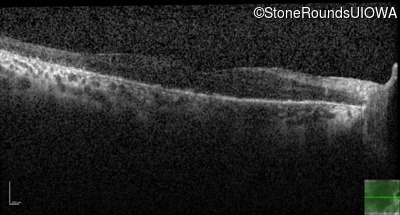

Age at visit: 60 years